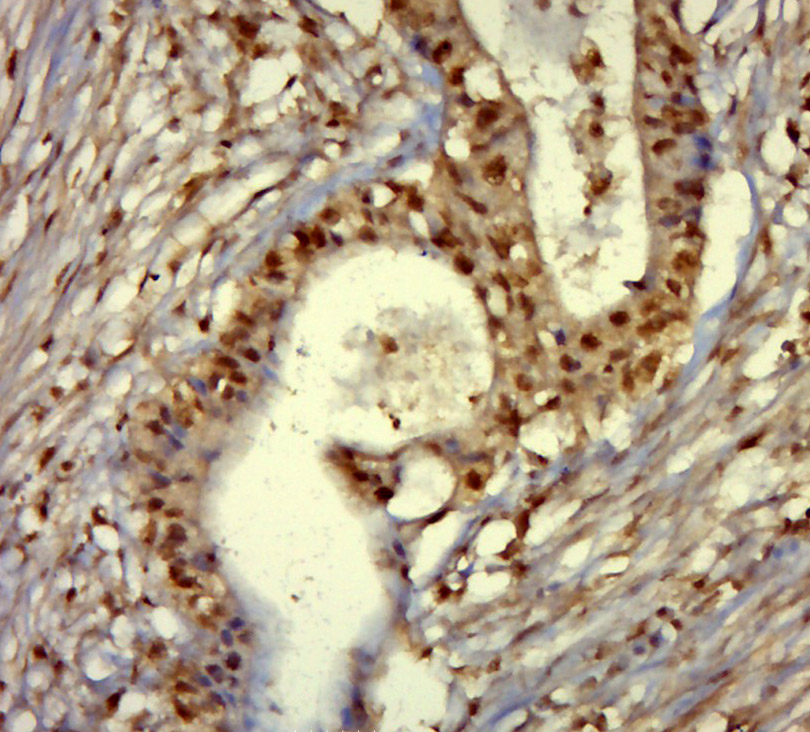

| 英文名称 | phospho-ETS2 (Thr72) Rabbit pAb |

| 中文名称 | 磷酸化癌基因ETS2抗体 |

| 产品应用 | IHC-P=1:100-500, IHC-F=1:100-500, IF=1:100-500 Not yet tested in other applications. |

| {IHC-P} | {1:100-500} |